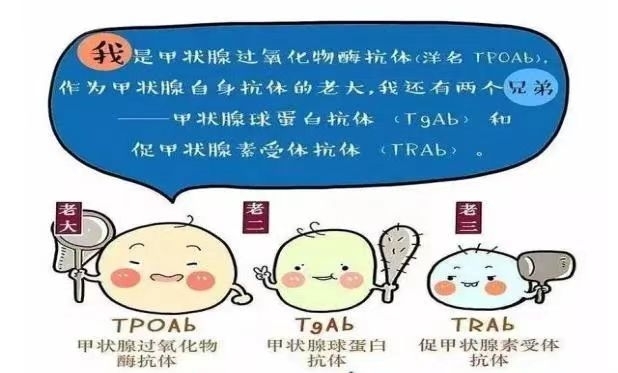

甲状腺是人体最大的内分泌腺,其所分泌的甲状腺激素是人体生长发育与新陈代谢不可缺少的激素。近年来,甲状腺疾病发病率逐年上升,甲状腺功能检查也非常普遍,除了比较常见的甲功五项、甲功八项,还有一项检验指标值得我们关注,那就是促甲状腺素受体抗体(TRAb),接下来我们一起了解一下吧。促甲状腺素受体抗体(th...

甲状腺是人体最大的内分泌腺,其所分泌的甲状腺激素是人体生长发育与新陈代谢不可缺少的激素。近年来,甲状腺疾病发病率逐年上升,甲状腺功能检查也非常普遍,除了比较常见的甲功五项、甲功八项,还有一项检验指标值得我们关注,那就是促甲状腺素受体抗体(TRAb),接下来我们一起了解一下吧。促甲状腺素受体抗体(th...